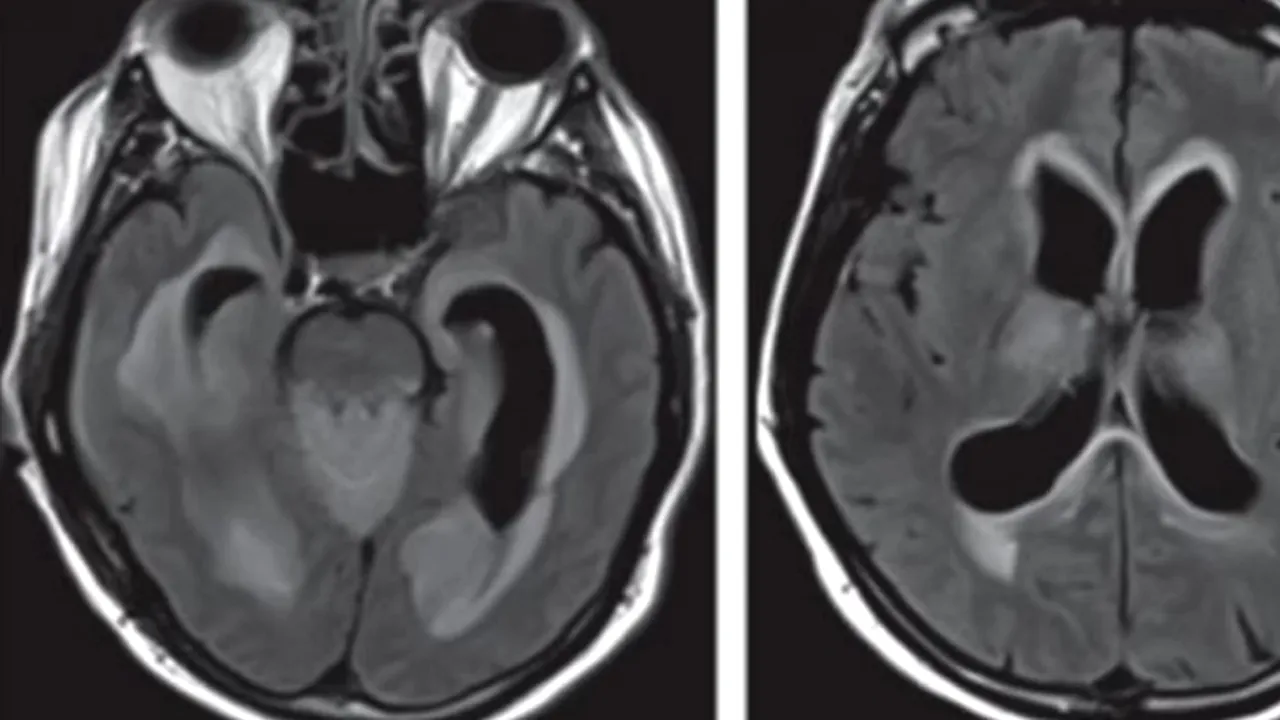

O săptămână mai târziu, starea acestuia s-a înrăutățit și pacientul a devenit mai puțin conștient. Medicii au presupus că avea o afecțiune severă la creier. Omul nu-și deschidea ochii la comenzile personalului medical. Un RMN a scos la iveală faptul că bărbatul avea un exces de lichid în creier, alături de alte leziuni ale acestuia.

Credit: Reproduced with permission from JAMA Neurology. 2018. doi:10.1001/jamaneurol.2018.0132. Copyright©2018 American Medical Association. All rights reserved.